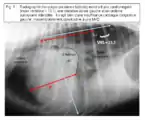

On l’a vu, dans la très grande majorité des cardiopathies du chien, on a très rapidement une dilatation, d’abord atriale puis plus ou moins rapidement ventriculaire. Cette dilatation est visible et mesurable très facilement à la radio par la méthode de l'index vertébral[6],[7],[8],[9] (cf. figure 9). Encore une fois, sans cardiomégalie, il y a peu de chances que l’on soit en présence d’une insuffisance cardiaque. - Ce chien présente-t-il des signes radiologiques de congestion ?

La radiographie est l’examen de choix pour visualiser la congestion : elle se traduit dans un premier temps par des dilatations vasculaires, puis par l’apparition d’œdème pulmonaire, d’abord interstitiel puis alvéolaire (présence de bronchogrammes, cf. figure 10).

Figure 9 : Radiographie thoracique (incidence latérale) montrant une cardiomégalie (index vertébral = 13,1), une dilatation atriale gauche et un œdème pulmonaire interstitiel : il s’agit bien d’une insuffisance cardiaque congestive gauche, vraisemblablement consécutive à une MVD.

Figure 10 : Radio thoracique incidence dorso-ventrale (CKC). Insuffisance cardiaque congestive sévère : œdème alvéolaire marquée. On note la présence de bronchogrammes aériques très visibles (flèches).